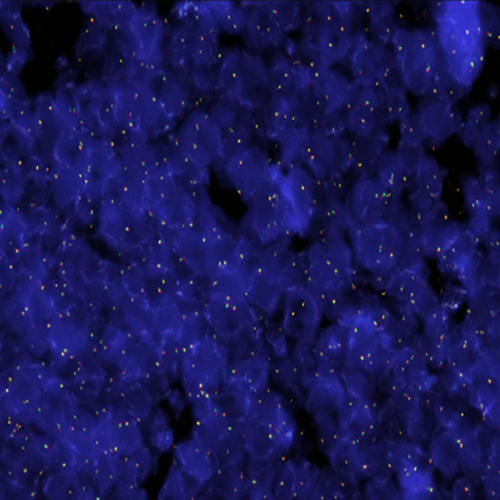

FGFR1 (8p11) Break probe hybridization to a tissue section showing a normal pattern.

FGFR1 has been implicated in the tumorigenesis of hematological malignancies, where it is frequently involved in balanced chromosomal translocations, including cases of chronic myeloid leukemia (BCR-FGFR1 fusion) and the 8p11 myeloproliferative syndrome/stem cell leukemia-lymphoma syndrome, which is characterized by myeloid hyperplasia and non-Hodgkin's lymphoma with chromosomal translocations fusing several genes, the most common being a fusion between ZNF198 and FGFR1. The FGFR1 (8p11) Break FISH probe is optimized to detect translocations involving the FGFR1 gene region at 8p11 in a dual-color assay on FFPE tissue sections.